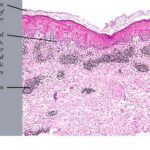

EM, as classically described by von Hebra, is a benign, self-limited condition with symmetric, fixed lesions, some of which evolve into typical targets composed of three concentric rings. The lesions are located primarily on the extremities (Fig. 9-26A). Bullous EM is a more severe form, which was defined by an international consensus group in 1993 as having typical targets or raised atypical targets with <10% of body surface area detachment . |

Histopathology. EM is considered the prototype of the vacuolar form of interface dermatitis . The early changes include vacuolization of the basal cell layer; tagging of lymphocytes along the dermal-epidermal junction; and a sparse, superficial, perivascular lymphoid infiltrate . Necrosis of individual keratinocytes in the basal unit occurs, which is the hallmark of EM. Because of its acute nature, there is an orthokeratotic stratum corneum. Mild spongiosis, papillary dermal edema, and extravasation of red blood cells are seen. As the lesion becomes more developed, there is a moderate lichenoid infiltrate of Iymphohistiocytes at the dermal-epidermal junction with exocytosis. More apoptotic keratinocytes within and above the basal epidermal layer are present. The |

intensity of epidermal necrosis varies from vacuolated individual keratinocytes surrounded by lymphocytes (satellite cell necrosis) at the basal unit to confluent necrosis in association with intraepidermal and subepidermal vesicles. The dermal infiltrate comprises lymphocytes and histiocytes. Eosinophils may also be present. Although one study has noted a significant number of eosinophils in drug-induced EM, this has not been noted by others. In the authors’ estimation, a generous number of eosinophils exclude EM. One study has found that an acrosyringium concentration of apoptotic keratinocytes in EM is a clue to a drug etiology . In early lesions of SJSITEN, apoptotic keratinocytes are observed scattered in the basal layer of the epidermis. In established lesions, there are numerous necrotic keratinocytes, even full-thickness epidermal necrosis, and a subepidermal bulla. The dermal inflammatory infiltrate is sparser in TEN than in EM (Fig. 9-278). Extravasated erythrocytes are commonly found within the blister cavity. Melanophages within the papillary dermis occur in late lesions. Eccrine epithelium shows a variety of changes from basal cell apoptosis to necrosis of the duct. |

In general, EM shows less epidermal necrosis, more dermal inflammation, and exocytosis, whereas SJS and TEN reveal more epidermal necrosis, less dermal inflammation, and exocytosis. However, due to the overlapping histologic features among EM, SJS, and TEN, histologic examination-while important for recognizing the spectrum of disorders-is not reliable for classifying the disease. Correlation with clinical presentation is essential. |